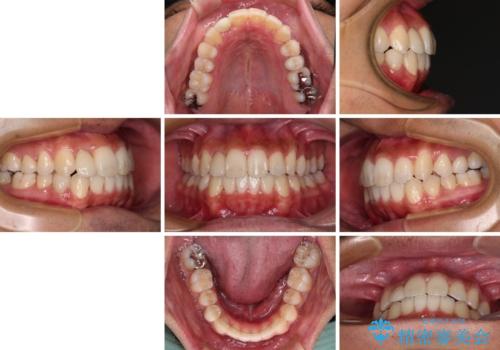

- 前歯のデコボコとクロスバイトを気にして来院された患者様です。

下顎の歯列弓に対して上顎歯列弓がやや小さく、側方の歯を中心にクロスバイトが見受けられました。

クロスバイトの改善は、インビザラインの場合歯髄壊死のリスクや咬み合わせが改善しきらないリスクがあるため、ワイヤー矯正をお勧めすることが多いですが、患者様の希望によりインビザラインにて矯正治療を行うこととしました。

後方に隠れていた上顎前歯は矮小歯であるため、矯正治療の途中でオールセラミッククラウンを装着し、左右対称の大きさでの仕上がりを目指すこととしました。

奥歯の咬み合わせは接触が少なく物足りないように見えますが、患者様としては十分に咬むことができるとのことでした。